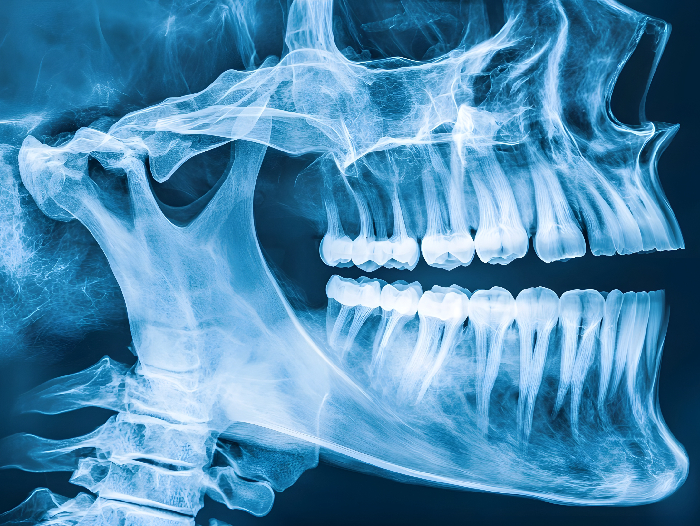

L’equip investigador del projecte europeu HYDROHEAL desenvoluparà micropartícules encapsulades en hidrogels bioresorbibles i autoenduribles, que permetran incorporar i transportar diversos principis actius farmacològics. Aquests biomaterials actuaran com a suport temporal per a la regeneració òssia i, alhora, permetran l’alliberament controlat i dirigit dels principis actius, millorant l’eficàcia del tractament i reduint significativament el risc d’infecció i de rebuig dels implants. El projecte se centra a desenvolupar nous biomaterials per al tractament de fractures vertebrals i alveolars (a la mandíbula, a la base de les dents), especialment en casos complexos derivats de l’osteoporosi, càncer o traumatismes.

A la Universitat Politècnica de Catalunya - BarcelonaTech (UPC), el projecte està coordinat pel catedràtic Conrado Aparicio, professor d'Investigació ICREA, director del grup de recerca Bioinspired Oral Biomaterials andInterfaces (BOBI) i investigador del Departament de Ciència i Enginyeria de Materials (CEM) de la UPC, que explica que “els materials que es fan servir per substituir l’os sovint s’infecten. Per lluitar contra aquest fet, els materials desenvolupats en el projecte porten agents antibacterians. El nostre grup avaluarà, en condicions que simulen el cos humà, com els bacteris s’adhereixen als materials desenvolupats i, per tant, determinarem quines són les millors estratègies per prevenir aquest tipus d’infeccions òssies”.